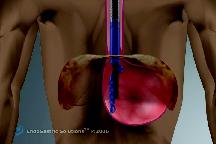

Η ανάγκη για μιά νέα μέθοδο αντιμετώπισης της ΓΟΠΝ, ισάξιας αποτελεσματικότητας με την Nissen αλλά χωρίς τους περιορισμούς και τα προβλήματα της, οδήγησε στη δημιουργία διαφόρων ενδοσκοπικών μεθόδων, οι οποίες στην πλειοψηφία τους απέτυχαν. Εξαίρεση αποτελεί η διαστοματική θολοπλαστική EsophyX. Η μέθοδος EsophyX είναι μία χειρουργική τεχνική όπου η γαστροοισοφαγική βαλβίδα διορθώνεται από το εσωτερικό του στομάχου. Με χρήση γενικής αναισθησίας η συσκευή εισάγεται από το στόμα (εικ.1), με την βοήθεια γαστροσκοπίου, και φθάνει στο στομάχι ενδοαυλικά (εικ.2). Με ανάστροφη όραση γίνεται συρραφή και επανακατασκευή της γαστροοισοφαγικής συμβολής με ειδικά clips που τοποθετούνται σε όλο το πάχος του τοιχώματος του στομάχου (εικ.3). Όταν υπάρχει μικρή διαφραγματοκήλη ανατάσσεται με την εισαγωγή και τοποθέτηση του οργάνου.

Εικόνα 1: H συσκευή εισάγεται από το στόμα.